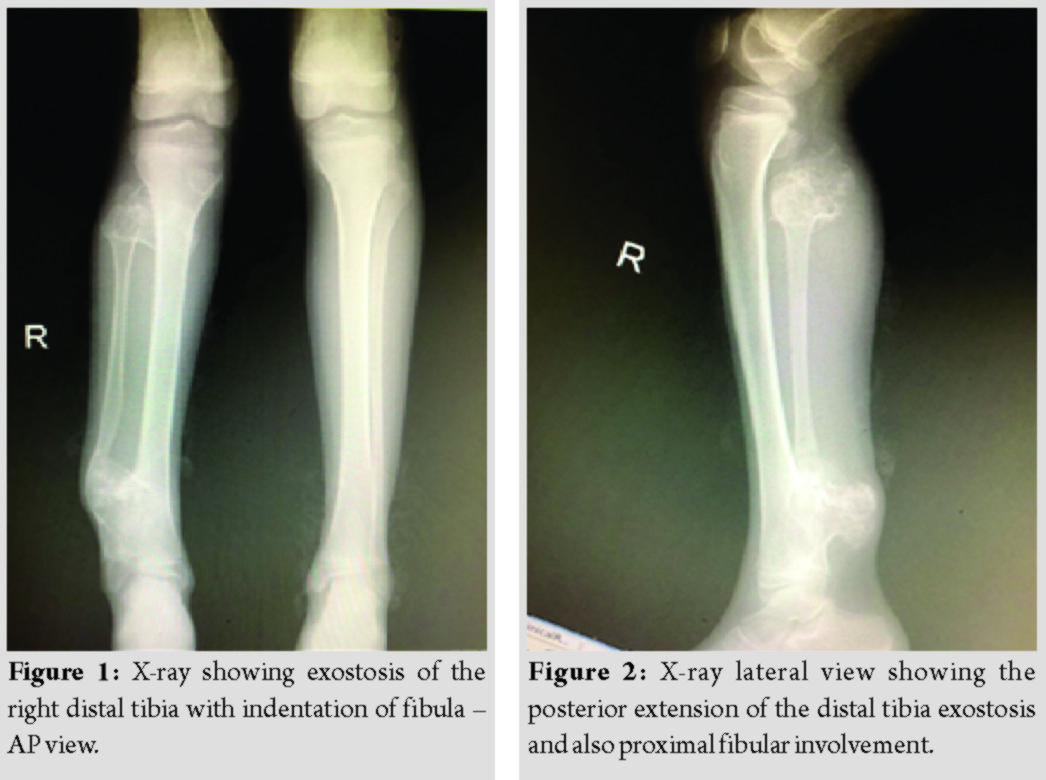

A 10-year-old female patient presented with a complaints of painless swelling around both the knees, right ankle, and left wrist which was first noticed at the age of 6 years and was gradually progressive. The patient started developing pain and deformity at the right ankle for 2 years, which was gradually progressive and had a difficulty in walking since then. There was no history of trauma, fever, weight loss, loss of appetite, and no other constitutional symptoms. Family history of multiple hereditary exostosis was present in father and younger male sibling. On examination, swellings were present over the medial and posterolateral aspect of the distal femur region, in posterolateral aspect of the right proximal tibia and posterolateral aspect of the right distal tibia, which were bony hard in consistency and immobile. The patient had varus deformity in the distal third of the right leg with no distal neurovascular deficit. X-rays of both knees, both ankles, both wrists, and full length both tibia taken in two planes which confirmed the bony exostosis and showed flattening/distortion of the right fibula by large exostosis of the distal tibia and ankle mortise appeared to be preserved (Fig. 1, 2).

Two-dimensional and three-dimensional computed tomography scan of the right lower limb was taken to know the extent of the exostosis and pre-operative planning, which suggested multiple osseous outgrowths in the lower end of femur, upper tibial metaphysis, distal tibia and proximal fibular metaphysis (Fig. 3, 4). All the swellings showed the continuation with medullary cavity of long bones. The largest lesion was measuring 4.8 × 3.4 × 3.1 cm in size in the posterolateral aspect of the right distal tibial metaphysis, which was indenting the fibula with bowing deformity, the knee and ankle joint movements appeared normal.